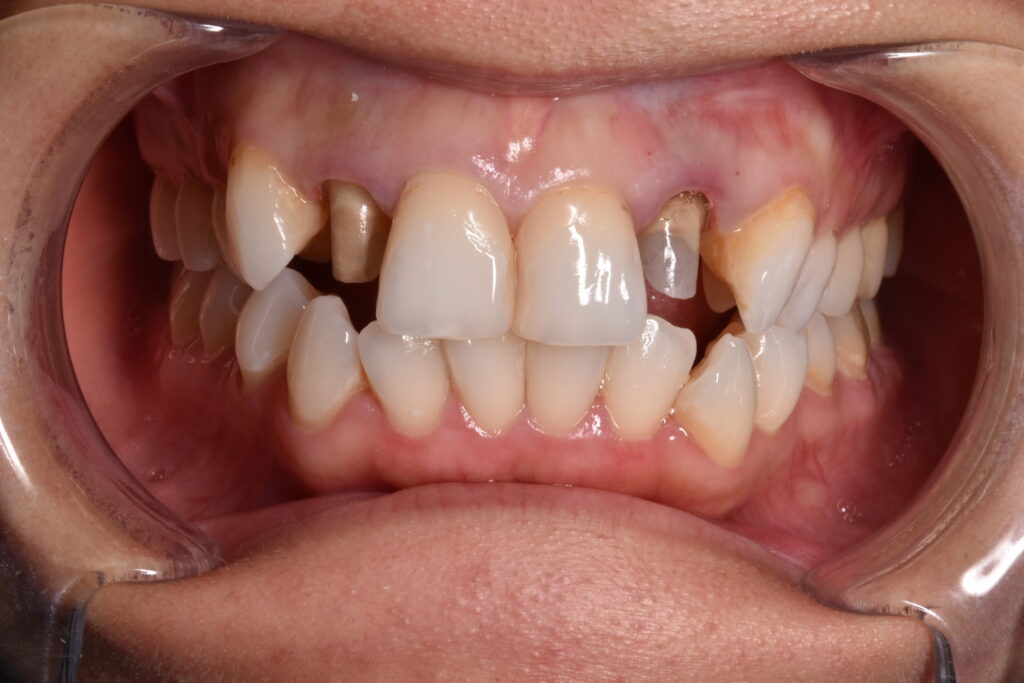

モニター様③

右の前歯の歯ぐきの黒ずみと古い被せ物のやりかえ治療をしています。歯の高さが左右で違うため歯肉整形をしています。*さくらセラミックプラン